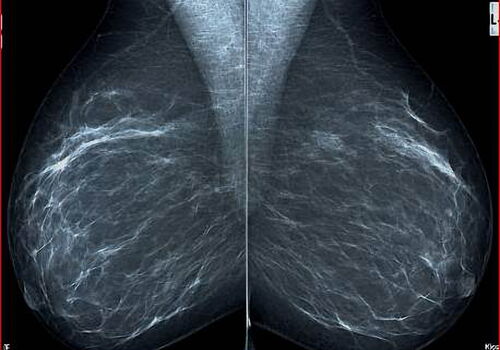

Es werden pro Mammogaraphieuntersuchung in der Regel pro Brust 2 Aufnahmen und unterschiedlichen Richtungen angefertigt. Hier seitlich/schräge Abbildungen -

Hier die andere Aufnahmen mit senkrechter Abbildung